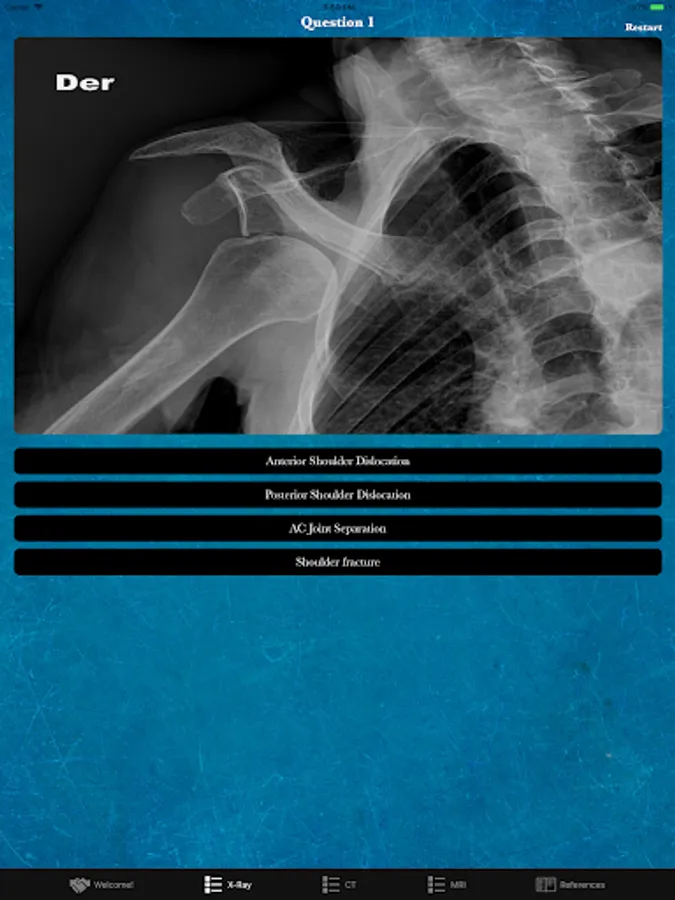

Rad Quiz is a free app developed as an introductory educational tool to expand your knowledge of medical imaging! Take our 20 question quizzes and evaluate your areas of strength and weakness. The quizzes test out three imaging modalities including X-ray, CT, and MRI. To learn more use our References tab to read up on the questions you missed. The content spans multiple specialities to give you a variety of content!